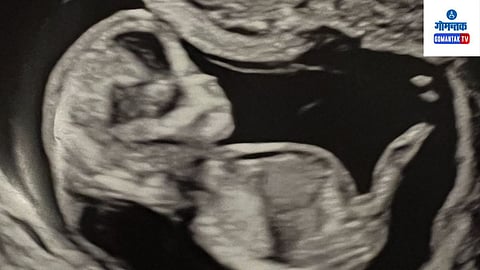

25 thousand rupees and killing of 900 embryos, the act of gang of doctors shook Bangalore: गलुरू शहर पोलिसांनी म्हैसूर आणि मंड्यामध्ये चालत असलेल्या एका मोठ्या लिंग निर्धारण रॅकेटचा पर्दाफाश केला असून, दोन वर्षात 900 हून अधिक भ्रूणांचा गर्भपात केल्याप्रकरणी दोन डॉक्टरांसह पाच जणांना अटक केली आहे.

आरोपी म्हैसूर येथील माथा हॉस्पिटलमध्ये हे बेकायदेशीर कृत्य करत आणि दर महिन्याला सुमारे 22 ते 25 गर्भांचा गर्भपात करत.

आरोपी केवळ बेंगळुरूच नव्हे तर जवळपासच्या जिल्ह्यांतील आणि उत्तर कर्नाटकातील महिलांची ओळख करून त्यांना गर्भपातासाठी आणत असत. काही लोक लिंग चाचणीसाठीही आले होते. नंतर ते स्त्री भ्रूणाचा गर्भपात करायचे आणि त्याच्या मोबदल्यात मोठी रक्कम आकारायचे.

वीरेशला अटक केल्यावर ही बाब उघडकीस आल्याचे बायप्पनहल्ली पोलिसांनी सांगितले. चौकशीत आरोपीने दोन वर्षात सुमारे 900 भ्रूणांचा गर्भपात केल्याची कबुली दिली.

प्रत्येक गर्भपातासाठी, आरोपी रुग्णांकडून 25,000 रुपये आकारायचे. पोलिसांनी स्पष्टीकरण देताना सांगितले की, रिझमा आणि मीना वीरेश, नयन कुमार, सिद्धेश आणि शिवलिंग गौडा यांच्या संपर्कात होत्या.